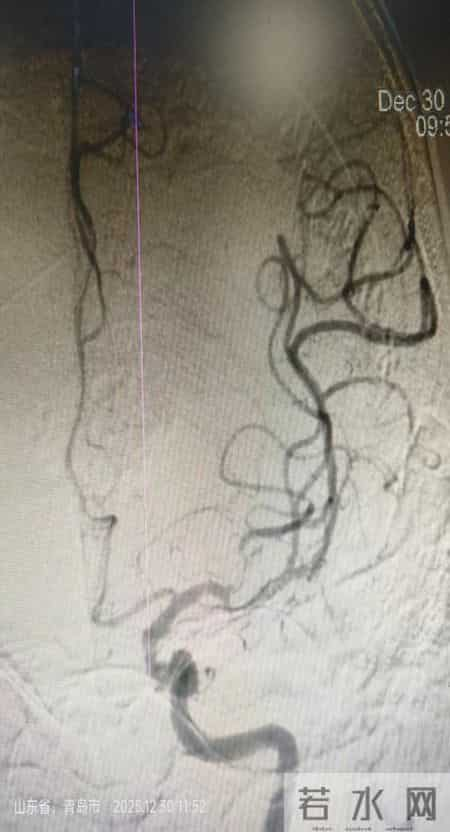

患者B为店子镇昌里村一名82岁的崔大爷,晨起发现右侧肢体无力,伴失语、双眼向左侧凝视,紧急送往平度市第三医院。急诊一键启动卒中绿色通道,经CT、MRI+MRA检查,确诊为一侧大脑中动脉闭塞,情况危急。神经内科介入团队评估后,直接上台取栓。刘文华副主任医师、高学松主治医师配合默契,介入手术室通力合作。术中仅1次抽吸便取出块状红色血栓,术后复查显示闭塞血管完全再通(mTICI 3级),术后即时右侧肢体肌力4+级,出院时患者恢复良好,行走自如。